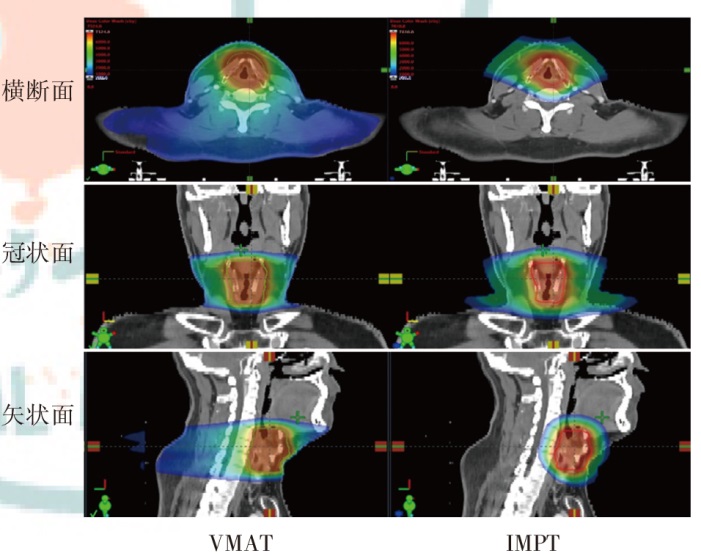

目的探索质子调强放疗(IMPT)和光子容积弧形调强放疗(VMAT)应用于典型头颈部恶性肿瘤的剂量学特点。方法以2023年12月至2024年12月山东省肿瘤防治研究院(山东省肿瘤医院)收治的鼻咽癌、腮腺癌和喉癌患者各1例为研究对象,分别根据靶区和危及器官限值的临床处方要求制定IMPT和VMAT计划。评估3例患者两种计划的靶区适形指数(CI)、均匀性指数(HI)和梯度指数(GI),并评估危及器官的剂量学指标。结果鼻咽癌、腮腺癌和喉癌患者IMPT计划的CI分别为0.70、0.72和0.67,HI分别为0.11、0.08和0.08,GI分别为3.08、2.49和3.75;VMAT计划的CI分别为0.77、0.82和0.91,HI分别为0.12、0.10和0.04,GI分别为3.67、2.63和3.45。IMPT计划的CI略低于VMAT计划,IMPT计划的HI与VMAT计划相当,鼻咽癌和腮腺癌患者IMPT计划的GI低于VMAT计划,喉癌患者IMPT计划的GI高于VMAT计划,且均在临床接受范围。IMPT计划在鼻咽癌、腮腺癌和喉癌治疗中表现出显著的剂量优势:对于鼻咽癌患者,IMPT计划的左、右晶体Dmax比VMAT分别降低了54.1%和50.4%,口腔和喉头的Dmean分别降低了40.5%和49.6%。对于腮腺癌患者,IMPT的脑干和脊髓Dmax比VMAT分别降低了66.2%和40.5%。对于喉癌患者,IMPT的脊髓Dmax比VMAT降低了77.0%,而甲状软骨Dmean比VMAT增加了8.0%。对于患者体内的额外剂量,以患者体内10%、30%和50%的处方剂量区域所占的绝对体积为例,鼻咽癌患者IMPT比VMAT计划分别降低了29.7%、29.6%和34.9%,腮腺癌患者IMPT比VMAT计划分别降低了61.0%、39.7%和17.4%,喉癌患者IMPT比VMAT计划分别降低了63.9%、31.7%和4.1%。结论相比VMAT计划,IMPT计划可有效降低头颈部肿瘤靶区附近大部分危及器官的受照射剂量,但对于紧邻靶区的串型器官,其剂量可能更高,需要引起关注。

ObjectiveTo investigate the dosimetric characteristics of intensity modulated proton therapy (IMPT) and photon volumetric modulated arc therapy (VMAT) in typical head and neck malignant tumors.MethodsThree types of typical head and neck tumors (nasopharyngeal carcinoma, parotid gland carcinoma, laryngeal carcinoma) treated at Shandong Cancer Hospital and Institute from December 2023 to December 2024 were taken as research subjects. IMPT and VMAT radiotherapy plans were created according to clinical prescription requirements of target and organs at risk limits respectively. The conformity index (CI), homogeneity index (HI) and gradient index (GI) for target coverage of two radiotherapy plans were evaluated for 3 patients, as well as the dosimetric indicators of organs at risk.ResultsThe CI of IMPT for nasopharyngeal carcinoma, parotid gland carcinoma and laryngeal carcinoma were 0.70, 0.72 and 0.67, respectively. The HI were 0.11, 0.08 and 0.08, respectively. The GI were 3.08, 2.49 and 3.75, respectively. The CI of VMAT plans were 0.77, 0.82 and 0.91, respectively. The HI were 0.12, 0.10 and 0.04, respectively. The GI were 3.67, 2.63 and 3.45, respectively. The results showed that CI of IMPT plan was slightly lower than that of VMAT plan, and HI of IMPT plan was comparable to that of VMAT plan, the GI of the IMPT plan for patients with nasopharyngeal carcinoma and parotid gland carcinoma was lower than that of the VMAT plan, and the GI of the IMPT plan for patient with laryngeal carcinoma was higher than that of the VMAT plan, and all were within the clinically acceptable range. The IMPT plan has demonstrated significant dose advantages in the treatment of nasopharyngeal carcinoma, parotid gland carcinoma and laryngeal carcinoma. For patient with nasopharyngeal carcinoma, the IMPT plan reduced the Dmaxof the left and right crystals by 54.1% and 50.4%, respectively, compared to VMAT plan, and reduced the Dmeanof the oral and laryngeal tissues by 40.5% and 49.6%, respectively. For patient with parotid gland carcinoma, IMPT plan reduced the Dmaxof the brainstem and spinal cord by 66.2% and 40.5%, respectively, compared to VMAT plan. For patient with laryngeal carcinoma, IMPT reduced spinal cord Dmaxby 77.0%, while thyroid cartilage Dmeanincreased by 8.0% compared to VMAT plan. For the additional dose in the patients' body, taking the absolute volumes occupied by the prescribed dose areas of 10%, 30%, and 50% in the patients' body as examples, IMPT plan of nasopharyngeal carcinoma patient decreased by 29.7%, 29.6%, and 34.9% compared to VMAT plan, respectively. IMPT plan of parotid gland carcinoma patient decreased by 61.0%, 39.7%, and 17.4% compared to VMAT plan, respectively. IMPT plan of laryngeal carcinoma patient decreased by 63.9%, 31.7%, and 4.1% compared to VMAT plan, respectively.ConclusionsCompared with VMAT plan, IMPT plan can effectively reduce the irradiation dose of most organs at risk near the target of head and neck tumors, but the dose of string organs close to the target area may be higher, which needs attention.